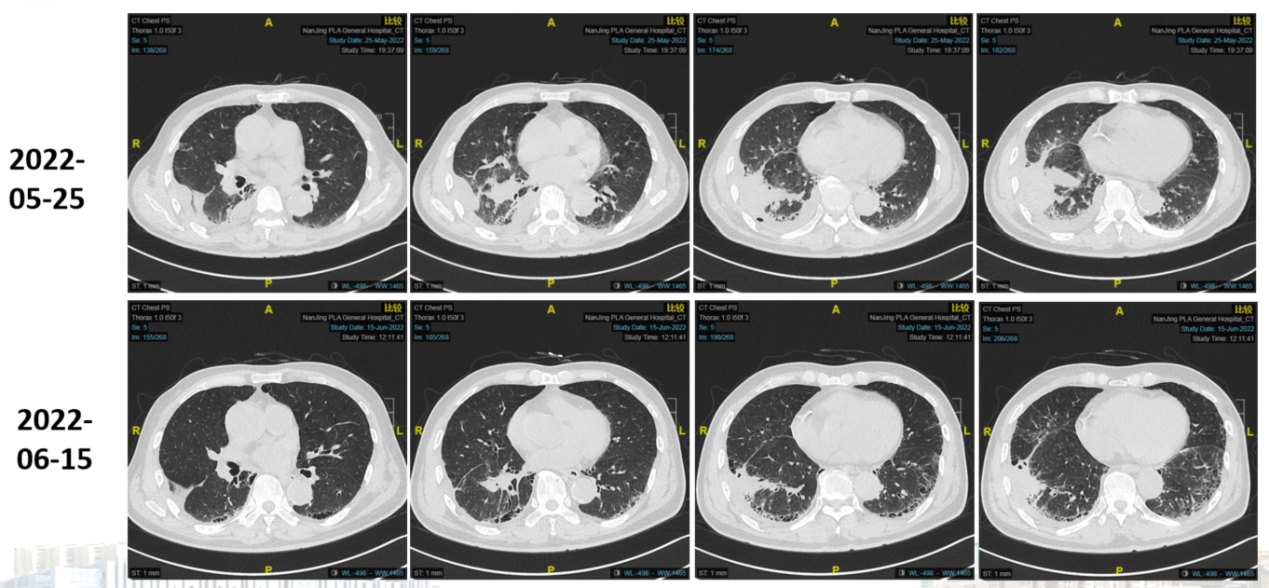

图2.2022-05-25胸部CT

于2022-05-25行第1周期化疗联合免疫治疗,具体方案:紫杉醇胶束360mg 静滴 d1+卡铂100mg 静滴 d1+舒格利单抗 1200mg 静滴 d1,辅以止吐、抗过敏治疗。

图片3.png

图3.治疗后评估

疗效评估为部分缓解(PR)。